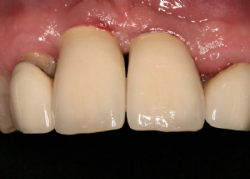

Aus der Vielzahl von Möglichkeiten wurde entschieden, Keramik-Kronen ebenfalls auf Basis von Zirkondioxid herzustellen (Cercon Ceram Kiss® von DeguDent®). Durch die Wahl einer metallfreien Basis kann die Ästhetik insbesondere am Gingivalrand entscheidend verbessert werden

Abbildung 7: Keramik-Kronen auf Zirkondioxid-Basis

Die Kronen wurden mittels Zement eingegliedert, wobei ein Produkt verwendet wurde, das eine möglicherweise später gewünschte Abnahme (TempBond® von Kerr®).

Abbildung 8: Kronen unmittelbar nach der Eingliederung